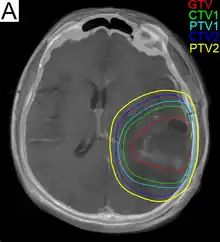

Radiation treatment planning for glioblastoma. GTV: gross tumor volume, CTV: clinical target volume, PTV: planning target volume.

Subsequent to surgery, radiotherapy becomes the mainstay of treatment for people with glioblastoma. It is typically performed along with giving temozolomide.[10] A pivotal clinical trial carried out in the early 1970s showed that among 303 GBM patients randomized to radiation or best medical therapy, those who received radiation had a median survival more than double those who did not.[69] Subsequent clinical research has attempted to build on the backbone of surgery followed by radiation. Whole-brain radiotherapy does not improve when compared to the more precise and targeted three-dimensional conformal radiotherapy.[70] A total radiation dose of 60–65 Gy has been found to be optimal for treatment.[71]